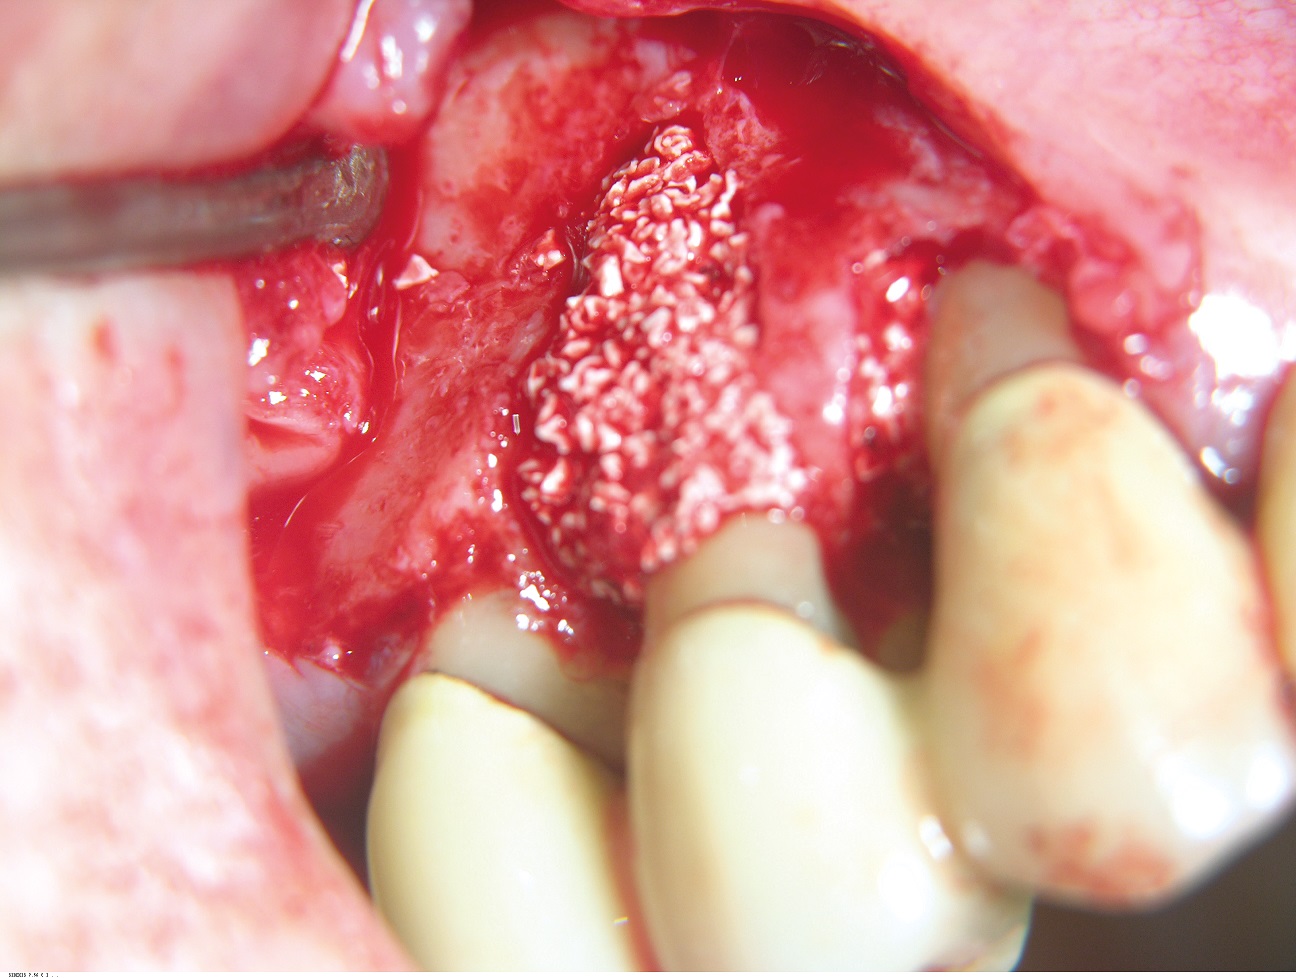

05/10 - Grafting of the bone defect with a mixture of cerabone® and autologous bone chips.GTR for the treatment of a deep three-dimensional intrabony defect using cerabone®, collprotect® membrane and Straumann® Emdogain® - Dr. T. Schwaar